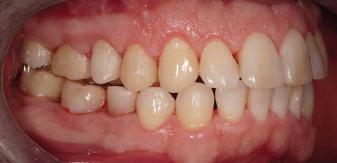

20 Dental Tribune Bulgarian Edition / октомври 2022 г. П ациентите със завършен растеж и скелетни проблеми обикновено представляват предизвикателство за ортодонт ската практика. Необходимостта от изваждане на зъби в комбинация с особеностите на възрастовата ортодонтия изисква особено внима ние. Фокусът върху критично важното значение на позицията на долните резци във връзка с дългосроч ната стабилност и постигането на оптимални оклузални взаимоотношения при затварянето на екстракционните пространства лесно може да излезе извън контрол. Когато към тези чисто кли нични проблеми се добави и стресът от натоваре ната практика, предизвикателството става още по-голямо. Всички тези фактори налагат използ ването на доказан подход с ясни и последовател ни стъпки, в което се разкрива силата на дисциплината „Алекзандър“ – предвидим протокол през целия процес на елиминиране на ротациите, ниве лиране на дъгите, затваряне на екстракционните пространства и финализиране на случая. Именно такъв е и случаят, който презентираме –екстракционен, скелетен клас 3 при възрастен па циент, лекуван по системата „Алекзандър“. ПРЕДВИДИМИ РЕЗУЛТАТИ ПРИ ПАЦИЕНТИ СЪС ЗАВЪРШЕН РАСТЕЖ И СКЕЛЕТЕН КЛАС 3, ИЗПОЛЗВАЙКИ ЕКСТРАКЦИОННО ЛЕЧЕНИЕ ПО ДИСЦИПЛИНАТА „АЛЕКЗАНДЪР“ Д-р Радой Димитров, България Преди започване на лечение клиничен случай | ортодонтия Фиг. 1а–1e Преди започване на лечение. Пациентът пристига в практиката с основното оплакване от невъзмож ност за нормално дъвчене. Снета е цялата необходима диагностична ин формация. Фиг. 1f–1h Снимки в профил и анфас. Фиг. 1i–1k Панорамна снимка, телерентгенография и анализ на телерент генография. Фиг. 1а Фиг. 1d Фиг. 1f Фиг. 1g Фиг. 1h Фиг. 1e Фиг. 1b Фиг. 1c Фиг. 1i Фиг. 1j Фиг. 1k

closed.

21Dental Tribune Bulgarian Edition / октомври 2022 г. ДИАГНОСТИЧНИ РЕЗУЛТАТИ: 1. Възраст на пациента: 21 години 2. Скелетен клас III (ANB 0) 3. Зъбен клас 3 4. Ръбцова захапка във фронта, кръстосана в дисталните участъци 5. Тясна горна челюст 6. Overjet – 0 мм, Overbite – 0 мм 7. Несъответствие на горната с долната средна линия 8. Единични контакти в ЦО 9. Хиподивергентен тип на растеж SN/MP – 33.5 10. Неравен гингивален контур 11. Неравна линия на усмивката 12. Тенденция за рецесии в долен фронт ПРЕПОРЪЧИТЕЛНО ЛЕЧЕНИЕ: Пълно ортодонтско лечение с метални брекети „Алекзандър“ Корекция на клас 3 захапката в областта на кучешките зъби с екстракция на първите пре молари в долна челюст Корекция на кръстосаната захапка в дистални участъци Коригиране на ръбцовата захапка във фронта Подобряване на ОJ и OB на пациента Стрипинг в долен фронт Подреждане на зъбите в горната и долната челюст Професионално хигиенизиране и профилактични дентални прегледи са препоръчителни на всеки 6 месеца. 1-ви месец След 1 месец са залепени брекети в горната челюст – поставена е еластична дъга. 016 NiTi. В долната челюст са елиминирани ротациите, поставена е стоманена дъга. 016SS, закалена с ток, и еластична верижка за затваряне на пространствата. 3-ти месец В долната челюст е поставена трета дъга – 17 x 25 NiTi с къси лигатури и верижка

В горната челюст се затварят пространствата с дъга .016SS и верижка. 5-и месец На 5-ия месец след залепяне на брекетите в долната челюст е поставена стоманена дъга 16 x 22 SS с четвъртито сечение, омега луп и тай бек. В горната челюст е поставена дъга 17 x 25 NiTi. Поради липсата на стабилни оклузални контакти са поставени лингвални верижки в областта на моларите, за да се предотврати нежелана ротация на 7-ите зъби. 6-и месец На 6-ия месец от началото на лечението са екстрахирани долните първи премолари, поставена е дъга 16 x 22 SS със затваряща чупка teardrop. Чупката се активира всеки месец по 1 мм с чинч-бек. клиничен случай | ортодонтия СТЪПКИ НА ЛЕЧЕНИЕТО Начало на лечението Лечението започва с поставяне на апарат за бърза експанзия в горната челюст. През първия месец от лечението са направени 24 оборота на апарата за експанзия. Залепени са брекети в долната челюст, поставена е дъга 17x25 CuNiTi, като са предпи сани клас 3 ластици (1/4”,4 1/2 oz) по време на сън, за да се осигури контрол върху торка на долните резци. Фиг. 2а Фиг. 3a Фиг. 4a Фиг. 3b Фиг. 4b Фиг. 3c Фиг. 4c Фиг. 3d Фиг. 4d Фиг. 3e Фиг. 4e Фиг. 5a Фиг. 5b Фиг. 5c Фиг. 5d Фиг. 5e Фиг. 6a Фиг. 6b Фиг. 6c Фиг. 6d Фиг. 6e Фиг. 7a Фиг. 7b Фиг. 7c Фиг. 7d Фиг. 7e Фиг. 2b Фиг. 2c Фиг. 2d

Dental Tribune Bulgarian Edition / октомври 2022 г.22 клиничен случай | ортодонтия 14-и месец В горната и долната челюст са поставени последни стоманени дъга с омега луп и тай бек – 17 x 25 SS с четвъртито сечение. Назначени е ластик за средната линия в комбинация с клас 3 ластик (1/4”, 6 1/2 oz). Контролни рентгенографии 13-и месец Екстракционните пространства са затворени. Направена е контролна панорамна снимка за оценка позицията на корените. Взето е решение за презалепване на брекетите на 12, 22 и пръстените на 36 и 46. 21-ви месец Средната линия в горната и долната челюст съвпадат. Ластиците са спрени. Свалени са пръстените и брекетите в горната и долната челюст, зигзаг ластици не са използвани поради благоприятните оклузални взаимоотношения. Фиг. 11j Ортопантомография в края на лечението. Фиг. 11k Телерентгенография след края на лечението. Фиг. 11l Анализ на телерентгенографията след лечението. Фиг. 11m Последователност на дъгите в горната и долната челюст Фиг. 11n Суперимпозиция на PreOp и PostOp ортопантомографии. 10-и месец Затварянето на пространствата е предвидимо и контролирано, без да се отварят пространства в зъбната дъга. Фиг. 8a Фиг. 8b Фиг. 8c Фиг. 8d Фиг. 8e Фиг. 10a Фиг. 10b Фиг. 10c Фиг. 10d Фиг. 10e Фиг. 9a Фиг. 9b Фиг. 9c Фиг. 9d Фиг. 9e Фиг. 9f Фиг. 11a Фиг. 11f Фиг. 11j Фиг. 11l Фиг. 11m Фиг. 11n Фиг. 11k Фиг. 11g Фиг. 11h Фиг. 11i Фиг. 11b Фиг. 11c Фиг. 11d Фиг. 11e

Dental Tribune Bulgarian Edition / октомври 2022 г. 23клиничен случай | ортодонтия реклама Лечението е продължило 21 месеца. Проведено е домашно избелване с индивидуални шини. За автора: Д-р Радой Димитров завършва с отличие Факултета по дентална медицина към МУ–София през 2015 г. В продължение на 5 години работи в няколко водещи практики в София, като през 2019 г. заедно със своята съпру га д-р Траяна Димитрова основават собствена практика в гр. Гоце Делчев –Dimitrovi Dental Care. Посещава редица курсове за повишаване на квалификаци ята, но най-сериозен тласък в развитието на ортодонтската си практика получава след завършването на комплексната ортодонтска програма, воде на от д-р Иван Горялов, базирана на дисциплината „Алекзандър“ – система с повече от 50 години опит в целия свят. Д-р Димитров е член на Българския изследователски клуб „Алекзандър“. Взе ма участие като гост-лектор в симпозиума с международно участие The Power of the Alexander Discipline, който се проведе на 14–15.05.2022 г. С д-р Ди митров можете да свържете на тел. +359885 252 025. Заключение Представеният случай е ярък пример за възможностите и красо тата на дисциплината „Алекзандър“ – приложен е утвърден под ход с ясни правила и са постигнати очакваните цели. Резулта тът ще бъде дългосрочно стабилен, тъй като са спазени всички правила, които се отнасят към максимално комфортната пози ция на зъбите в края на лечението. Постигнати са красива усмив ка и стабилна оклузия. ПОСТИГНАТИ РЕЗУЛТАТИ ОТ ЛЕЧЕНИЕТО 1. Коригирана ръбцова захапка 2. Коригирана клас 3 захапка в областта на ку чешките зъби 3. Коригирана кръстосана захапка в дисталните участъци 4. Коригиран овърджет и овърбайт 5. Разширена е горната зъбна дъга 6. Подредени зъби в горната и долната челюст 7. Постигната е стабилна захапка с множество контакти в ЦО 8. Драматично е подобрена дъвкателната функ ция 9. Подобрена е линията на усмивката ДРУГИ ПРОВЕДЕНИ ДЕНТАЛНИ ПРОЦЕДУРИ 1. Домашно избелване на зъбите 2. Екстракция на мъдреците Фиг. 12a Фиг. 12b Фиг. 12c Фиг. 12eФиг. 12d Фиг. 12f Фиг. 12g Информация за дати, цени и отстъпки www.bracescourses.com 0889 22 55 01 Практически курсове лектор д-р Иван Горялов Дисциплината „Алекзандър“ ПЪТЯТ КЪМ СУПЕРУСМИВКИТЕ 100% връщане на цялата сума, ако не сте удовлетворени след преминаване на Ниво 1 Директно и индиректно залепяне на брекети Анализ, диагноза и план на лечение Лечение на клас 2 дълбока захапка Екстракционно лечение Лечение на клас 3 отворена захапка НИВО 5НИВО 1 НИВО 2 НИВО 3 НИВО 4